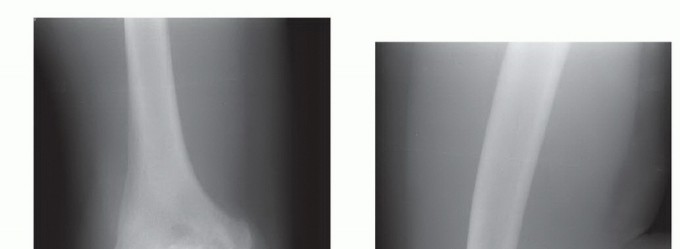

DEFINITION Panner Disease Panner disease is a condition in which there is compromised subchondral bone, poten…